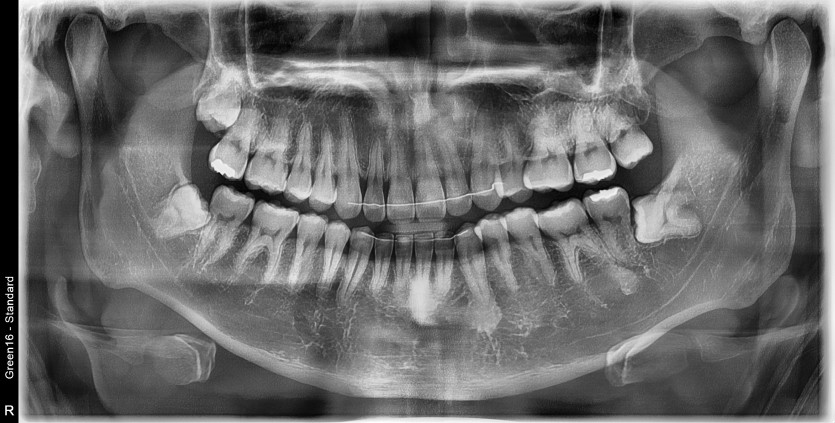

#18,28,38,48 사랑니 발치

구강외과 전문의가 당일 발치했습니다.